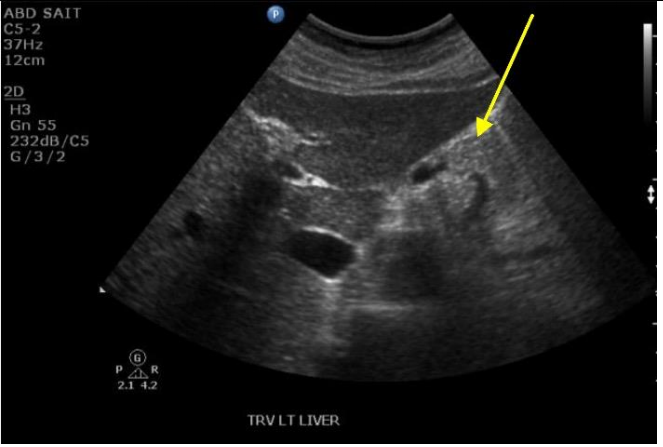

12

Q

What structure (at yellow arrow) is causing the shadow over LK?

A

RIbs